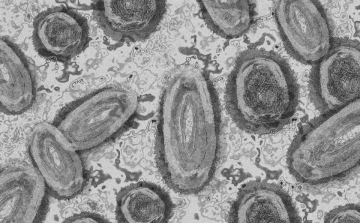

Magyar kutatók új antibiotikumot fejlesztettek ki, ami képes roncsolni a baktériumok sejtfalát

Ez a felfedezés azért is jelentős, mert az új szuperbaktériumok ellen a hagyományos antibiotikumok hatástalanok

Tovább nőtt a majomhimlő-fertőzöttek száma Magyarországon

Újabb két embernél igazolt majomhimlő-fertőzést a Nemzeti Népegészségügyi Központ (NNK) a 33. héten - augusztus 15-től 21-ig -, ezzel 64-re nőtt a magyarországi esetek száma.

Egy 3 év alatti gyermek fertőződött meg majomhimlővel Belgiumban

Belgiumban egy 3 év alatti gyermek fertőződött meg majomhimlővel - számolt be róla szerdán a Sudinfo hírportál.

Megfertőződött a majomhimlővel egy gyerek Németországban

Megfertőződött majomhimlővel egy négyéves kislány Németországban - jelentették kedden német hírportálok az országos közegészségügyi intézet (RKI) adatai alapján.